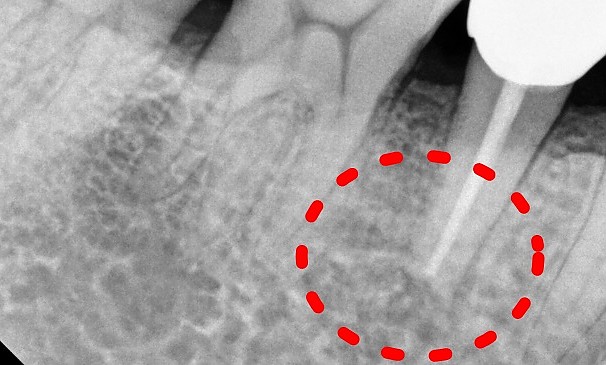

설OO님 전후사진 | 치료 기간 : 1주

치료 전

치료 후